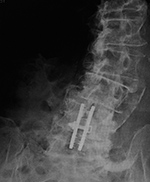

| 20 year-old woman with L1 vertebral body compression fracture treated with T12-L2 posterior spinal fusion using pedicle screws at T12 and L2 with connecting rods on each side. |